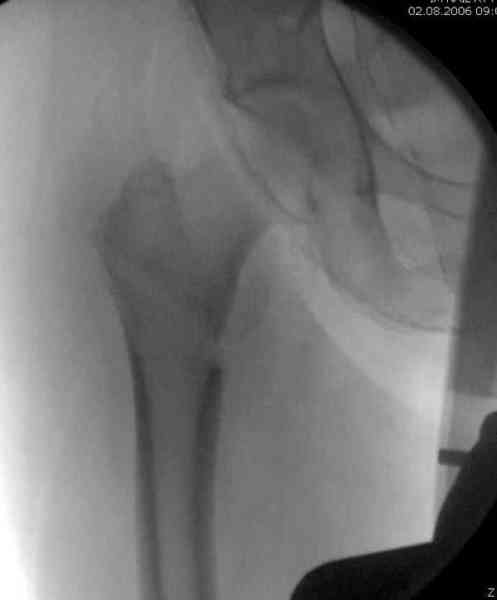

Здесь сканнированные снимки импланта и операционные снимки больной.